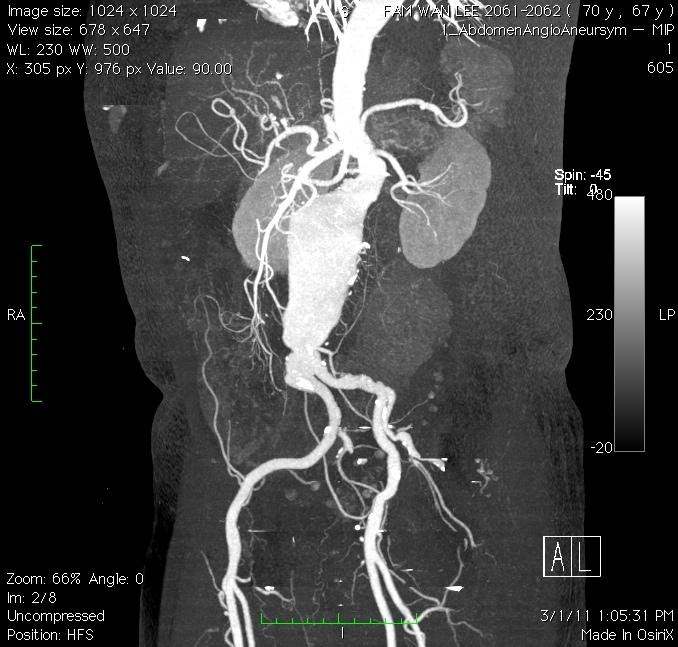

Modern diagnostic tools like ultrasonography (Figure 1) and computed tomography (CT) scan (Figure 2) makes the diagnosis much easier. The reported prevalence is around 4-8% in male and 1-2% in female after 70 year old. With ages beyond 80, the male to female ratio almost became 1:1.

Figure 1. Ultrasonographic picture of AAA

Figure 2. CT scan delineates the anatomy of AAA